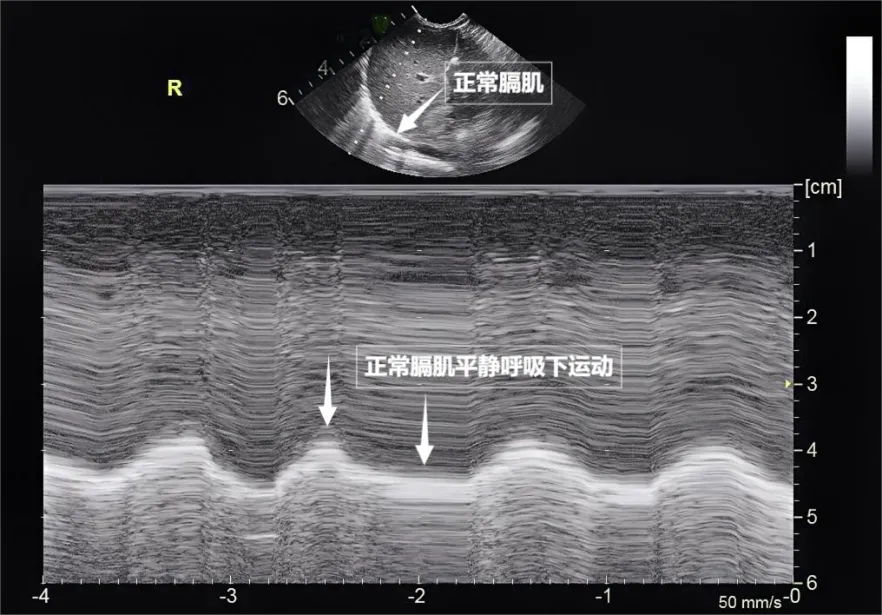

第三景:“呼吸的动力泵”的协同作战——呼吸肌肉

呼吸看似简单,实则是多组肌肉精密配合的“团体操”。肺部超声不仅能观察肺的形态,更能通过实时动态影像,“捕捉”这些呼吸肌的活动状态,为评估呼吸功能提供独特视角。膈肌是呼吸肌的“总指挥”,位于胸腔与腹腔之间。平静呼吸时,膈肌收缩下沉,胸腔容积扩大,空气自然吸入;舒张时,膈肌回升,肺部弹性回缩完成呼气。超声下可见膈肌呈光滑弧形,随呼吸规律上下移动(见下图)。肋间外肌则是“肋间隙的升降机”,收缩时上提肋骨,扩大胸腔前后径,辅助吸气。这对“黄金搭档”承担了日常呼吸70%以上的工作量,是维持呼吸的“主力军”。

图为正常膈肌超声表现

当身体需要更多氧气时(如上楼梯),斜角肌和胸锁乳突肌便会“增援”。在极端情况(如哮喘发作)下,腹壁肌群和肋间内肌会紧急出动。

肺部超声这位“侦察兵”,通过观察肌肉激活顺序、测量膈肌厚度与移动度、捕捉肌肉矛盾运动,动态评估呼吸肌肉的变化,早期发现呼吸系统“超负荷运转”的信号,为医生调整治疗方案提供精准依据。